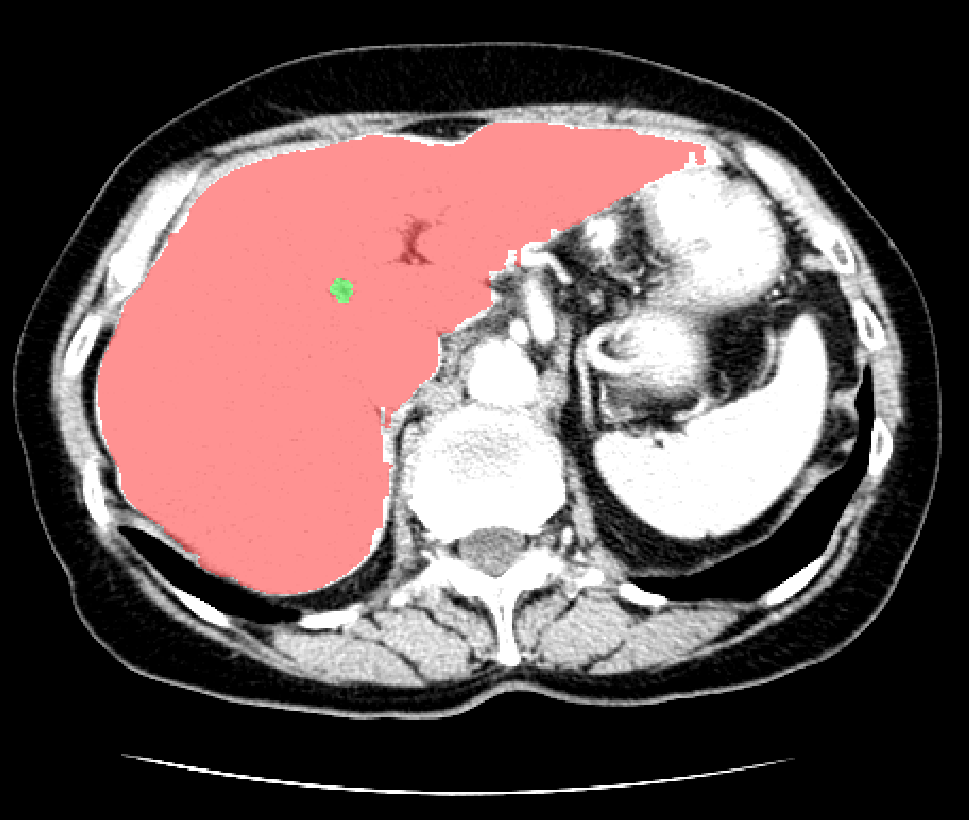

图6 分割结果

深度学习算法对一组CT扫描进行分割大概耗时15S,其效率明显高于医生阅片的效率。而且从分割结果中,我们可以计算获得肝脏体积,肿瘤数量,肿瘤体积,肝脏肿瘤负担等数量化的指标,更好地辅助医生进行诊断。